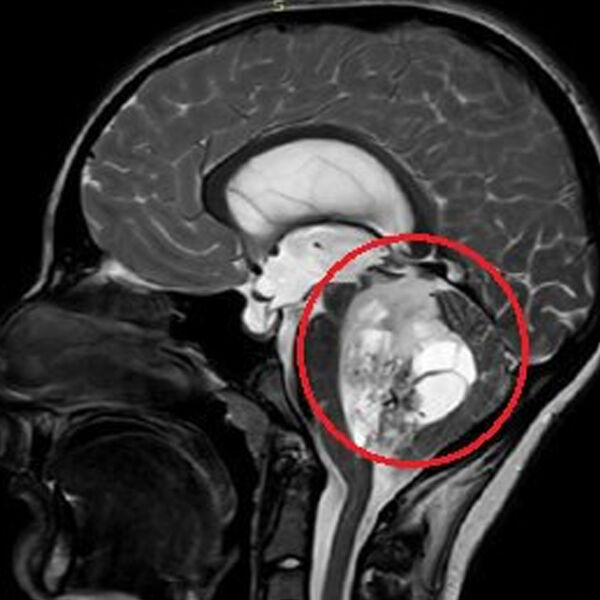

По словам медиков, юноша жаловался на постоянную тошноту и рвоту, которые не удавалось купировать консервативными методами. На обследовании специалисты обнаружили пятисантиметровую опухоль в задней черепной ямке. По словам врачей, ее дальнейший рост мог привести к нарушению жизненно важных функций мальчика.

«Сложность данного случая заключалась в том, что опухоль росла из области, которая отвечает за жизненно важные функции - любое, даже маленькое повреждение могли привести к тяжелым неврологическим осложнениям», — отметили нейрохирурги.